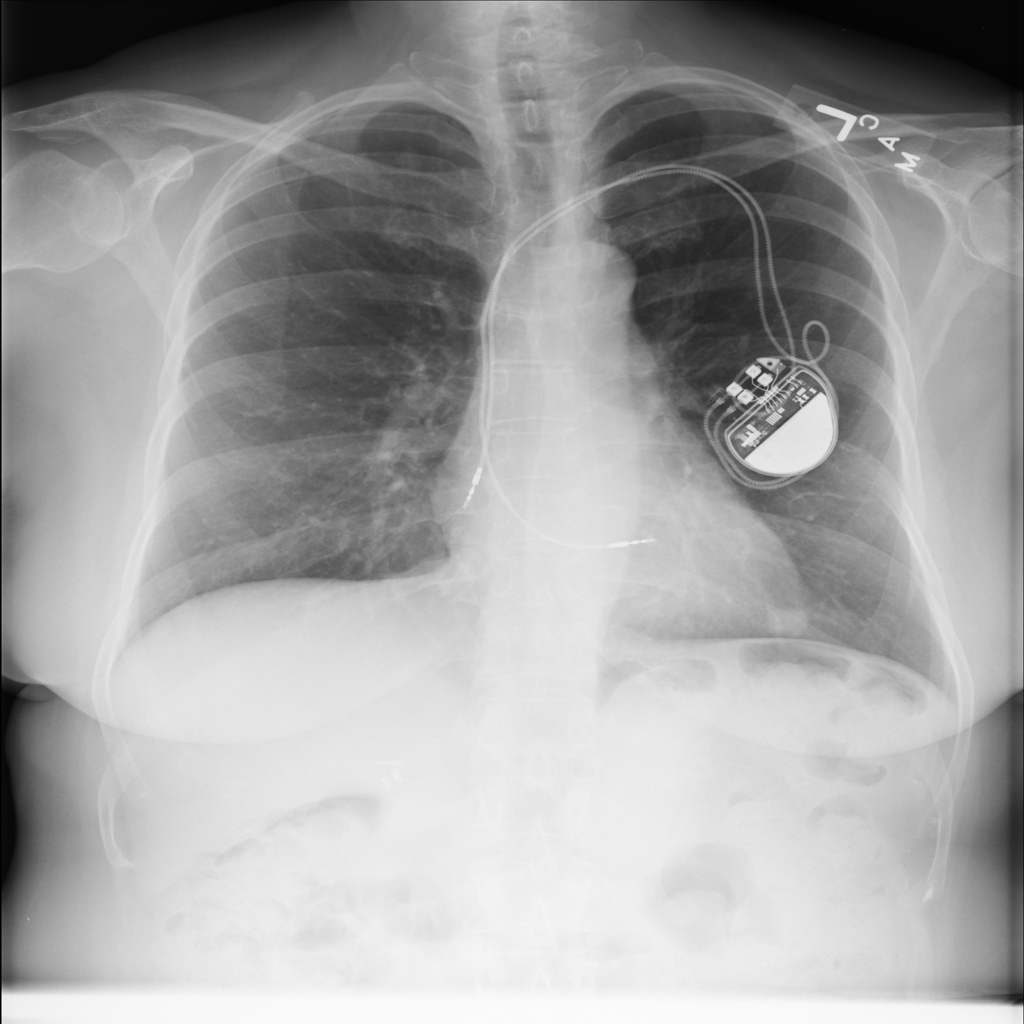

PAT-F3E7 · IMG-002Nodule

PAT-F3E7 · IMG-002

PA